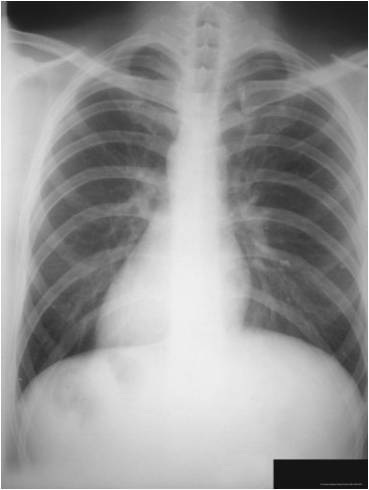

What does this x-ray illustrate?

bronchitis